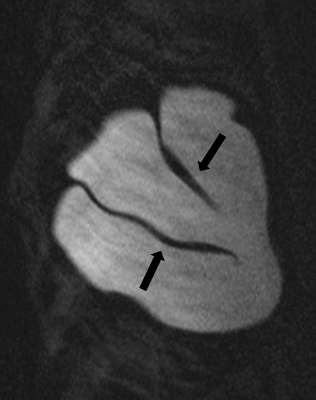

Minimally collapsed intracapsular rupture appears as a hypointense line that runs parallel to the fibrous capsule against the hyperintense extravasated silicone gelon silicone-sensitive MRI images, termed the “subcapsular line sign” (Figure 3).

Axial STIR MRI with arrows demonstrating subcapsular lines of bilateral intracapsular ruptures.

Figure 3: Axial STIR MRI with arrows demonstrating subcapsular lines of bilateral intracapsular ruptures.